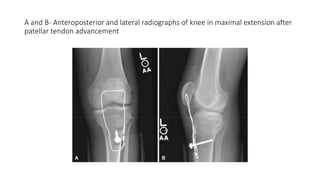

• The type of patellar tendon advancement depends on the skeletal

maturity of the patient

• If the physis is open, sharply divide the patellar tendon from the tibial

tubercle to avoid physeal injury and advance it under a periosteal flap

• If the physis is closed, transpose the tibial tubercle with the attached

patellar tendon distally and secure it with a compression screw

• Insert a 16-gauge wire or tension-band wire transversely through the

patella and the proximal part of the tibia to protect the repair (Fig)

A and B- Anteroposterior and lateral radiographs of knee in maximal extension after

patellar tendon advancement